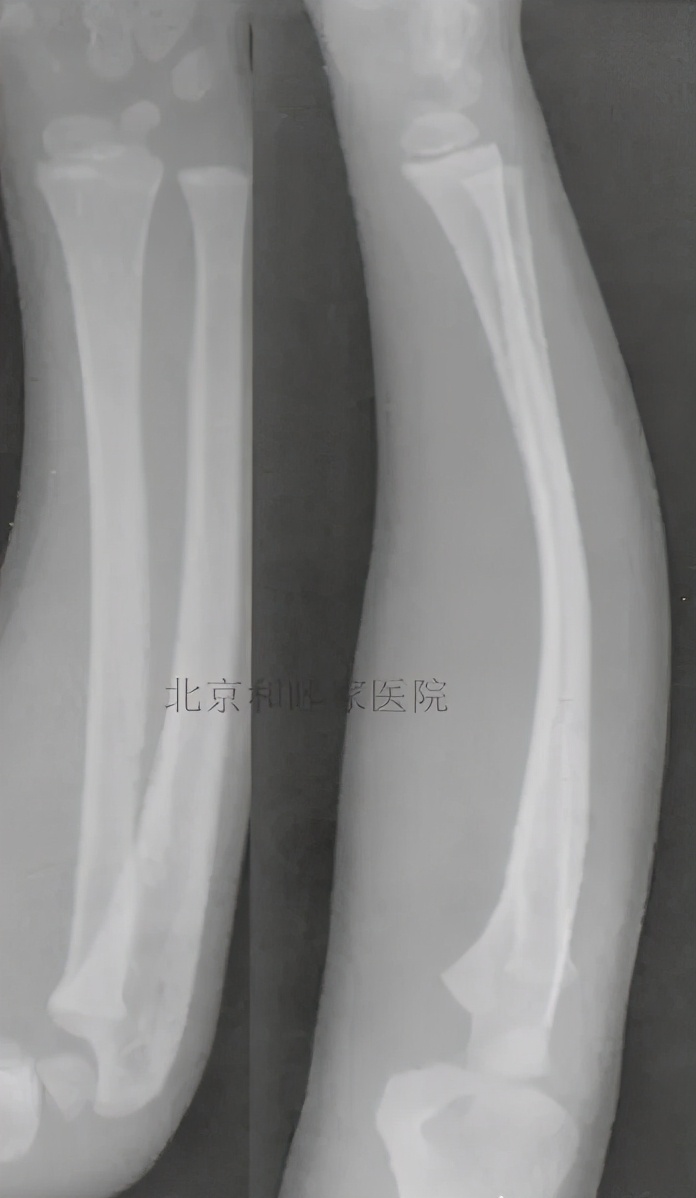

弯曲骨折(Bowing fracture)或塑性骨折(Plastic fracture):

弯曲骨折或塑性骨折的特点是骨头弯而不裂,如下图所示: